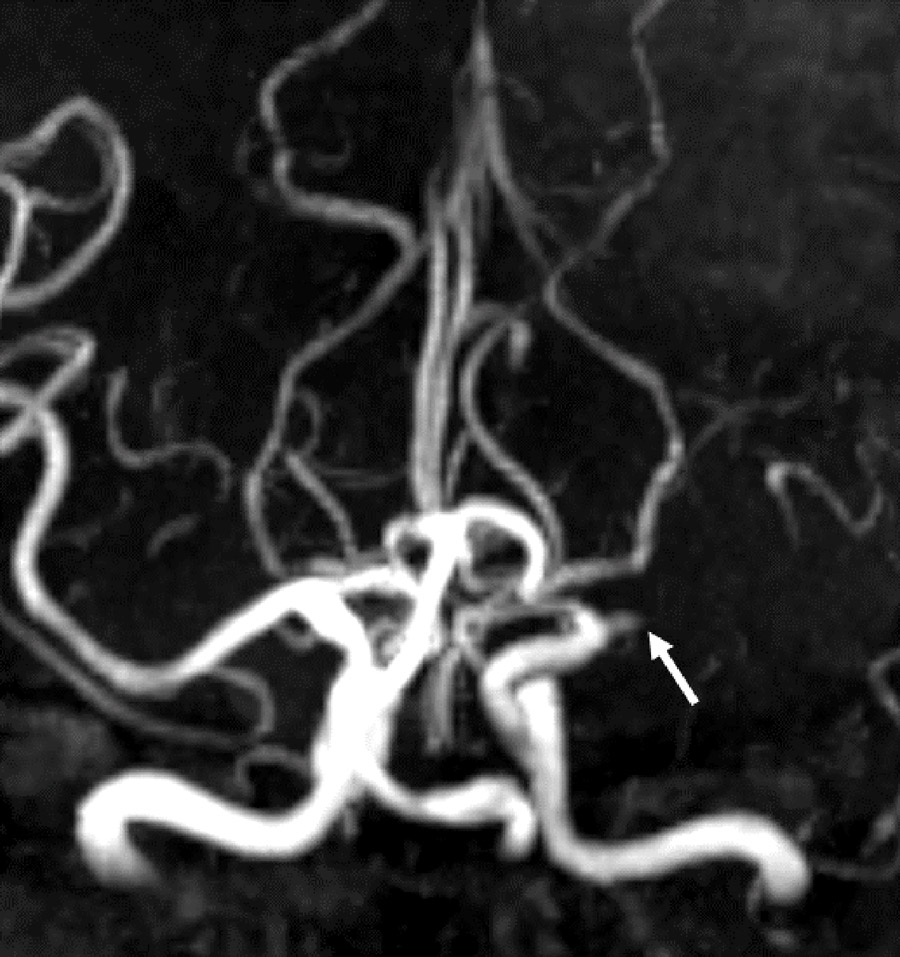

对245例患者进行了分析,发现ICAD病变处狭窄后低压力和高壁剪切应力与一年内再次中风的风险增加相关。简单地说,这些特征减少了流向脑组织的流量,对斑块施加了更大的压力,从而增加了进一步中风的机会。为了进一步研究ICAD,研究组使用了磁共振成像/计算机断层血管造影。这些脑成像技术使研究小组能够看到153名因ICAD而中风的患者的大脑和大脑中的血管。这种方法被用来识别中风机制,即动脉到动脉栓塞(流动的血凝块会阻塞血管)和低灌注(流向脑组织的流量减少)与一年之内复发风险增加(即第二次中风)有关。

然后研究研究组决定研究ICAD中的斑块形态。这是重要的,因为ICAD斑块形态在很大程度上无表明,与与心脏病发作相关的冠状动脉斑块等其他条件不同。理解斑块的形态,然后可以解释为什么与其他中风机制相比,动脉对动脉栓塞和低血量症更容易引起又一次中风。从本质上讲,小组想知道斑块形态类型是否是造成行程机制的原因。招募了180名中风患者,研究了一种优越的成像技术,称为三维旋转血管造影,其赋予优异的空间分辨率。